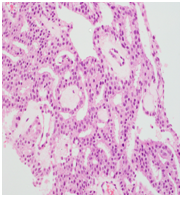

Trans-rectal ultrasound guided biopsy of the prostate confirmed the adenocarcinoma Gleason score 9 (4+5), while the mandibular lesion biopsy revealed metastatic prostate adenocarcinoma (Figures 6–8).

Figure 7 & 8 Prostate biopsy.